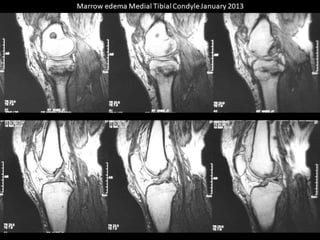

The document presents a detailed case study of a patient with transient osteoporosis of the hip (TOH) and spontaneous osteonecrosis of the knee (SONK) treated at Choithram Hospital & Research Centre in India. Over 20 years, the patient experienced multiple episodes of TOH and SONK with no history of trauma or co-morbidities, resulting in resolutions and recurrences of conditions. The information is intended for orthopedic surgery students and highlights personal experiences and case collections, with a disclaimer regarding content usage and potential controversies.